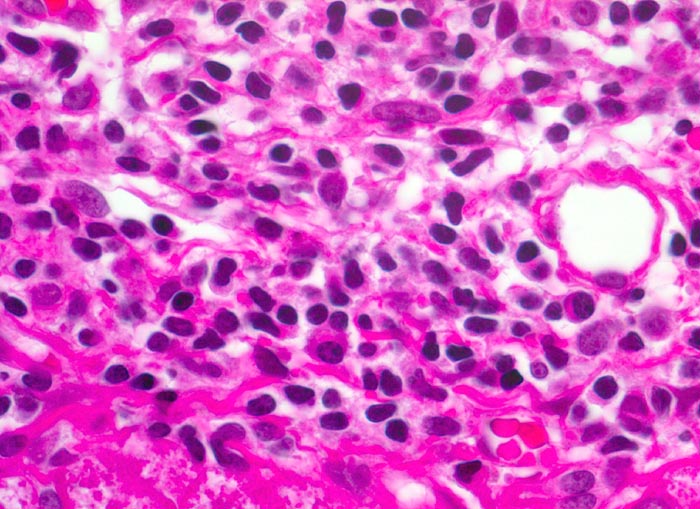

• Dichte mononukleäre portale und lobuläre Entzündungsinfiltrate mit Ausbildung von Lymphfollikeln in den Portalfeldern.

• Übergreifen der Entzündung auf das Parenchym (=Interface oder Grenzzonenhepatitis).

• Abgerundete hypereosinophile apoptotische Hepatozyten (Councilman-Körperchen).